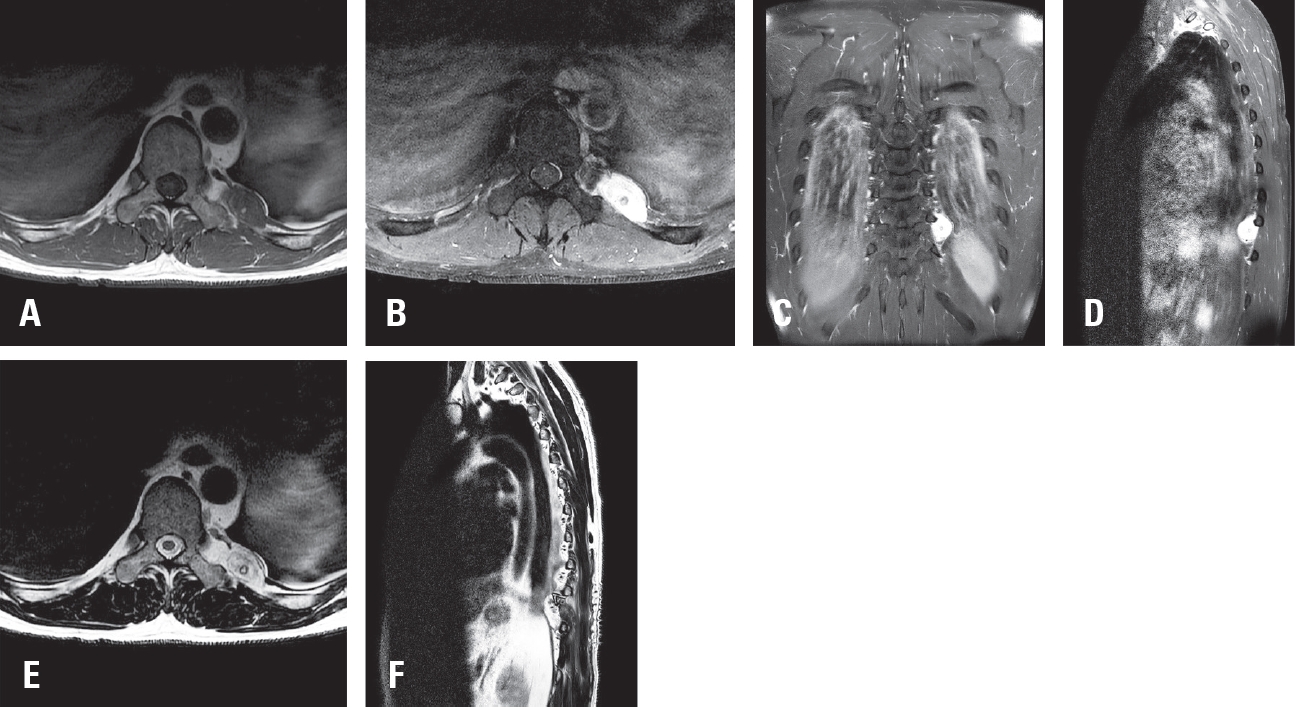

Magnetic resonance imaging (MRI) demonstrated a 2.8 cm ovoid, hypervascular mass at the T10–T11 level in the left posterior hemithorax, encasing the left 10th rib and adjacent to the left T10 transverse process. The mass showed hypointensity on T1-weighted images (

Fig. 1A), hyperintensity on T2-weighted images (

Fig. 1E,

F), and homogeneous enhancement after contrast administration (

Fig. 1B-

D). Based on these imaging characteristics, the lesion was initially suspected to be a schwannoma, and surgical resection was planned.

Fig. 1.Preoperative magnetic resonance imaging (MRI) of the thoracic spine. (A) Axial T1-weighted image showing a hypointense mass at the left T10–11 level. (B) Axial T1-weighted dolinium-enhanced image demonstrating homogeneous enhancement. (C) Coronal T1-weighted gadolinium-enhanced image showing the ovoid mass in the left posterior hemithorax. (D) Sagittal T1-weighted gadolinium-enhanced image delineating the extent of the mass. (E) Axial T2-weighted image showing a hyperintense lesion. (F) Sagittal T2-weighted image confirming hyperintensity of the mass.